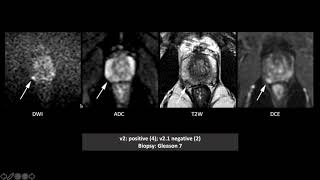

Prostate MRI: From Principles to Performance PI-RADS v2 and v2.1: Interobserver Agreement and Diagnostic Performance in PZ and TZ lesions

PI-RADS v2 and v2.1: Interobserver Agreement and Diagnostic Performance in PZ and TZ lesions